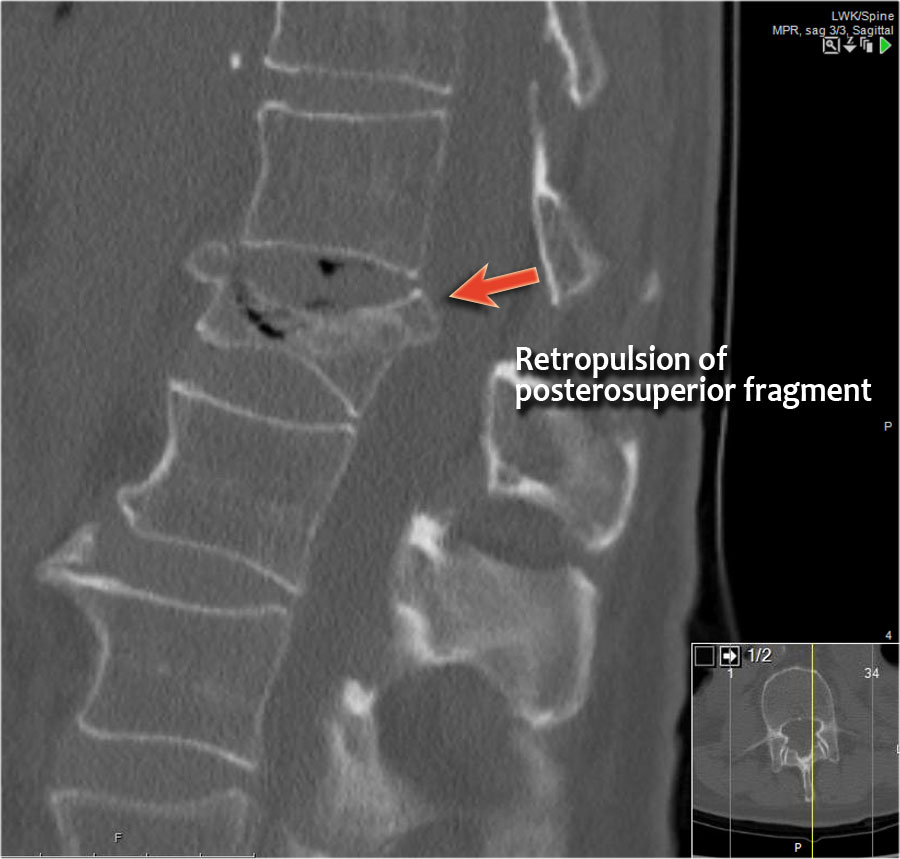

Mảnh xương góc sau trên thân đốt sống bị đẩy lùi ra sau (Retropulsion)

Hiện tượng mảnh xương bị đẩy lùi ra sau là đặc điểm điển hình của gãy vỡ, phân biệt rõ ràng với gãy nén đơn thuần.

Cuộn qua các hình ảnh.